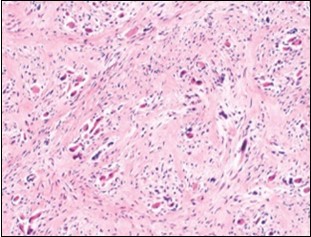

On microscopy, a collagen- rich, minimally cellular, fibrotic soft tissue nodule is exemplified which simulates a scar or conventional fibroma. The neoplasm is comprised of uniform, plump, fibroblastic or myo-fibroblastic cells encompassed in a collagen-rich stroma with infiltration and entrapment of skeletal myocytes 5, 6. Cogent histological examination depicts replacement of muscle fibres and muscle mass with fascicles of fibrous tissue comprised of mature fibroblastic cells, thereby conferring fibrosis 6. Figure 1, Figure 2, Figure 3, Figure 4, Figure 5, Figure 6, Figure 7, Figure 8.

Figure 7.Fibromatosis colli exhibiting fibroblasts, myo-fibroblasts and an abundant collagenous stroma with commixture of enlarged myocytes 14.

Figure 8.Fibromatosis colli enunciating fibroblasts, myo-fibroblasts and collagenous stroma with dispersed mature myocytes 14.